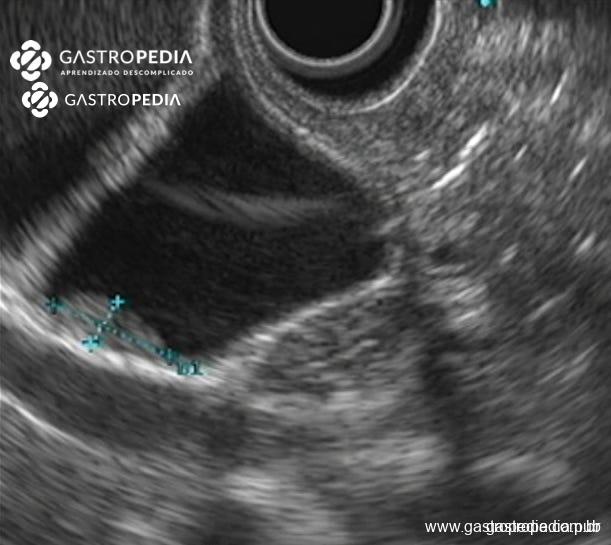

La ecografía endoscópica mejora la sensibilidad de la ecografía transabdominal, especialmente para el diagnóstico diferencial con cáncer de vesícula biliar.

Engrosamiento segmentario hipoecoico en el fondo de la vesícula biliar, de 11×5 mm, sugestivo de adenomiomatosis. Imagen cedida por la Dra. Julia Mayumi Gregorio.